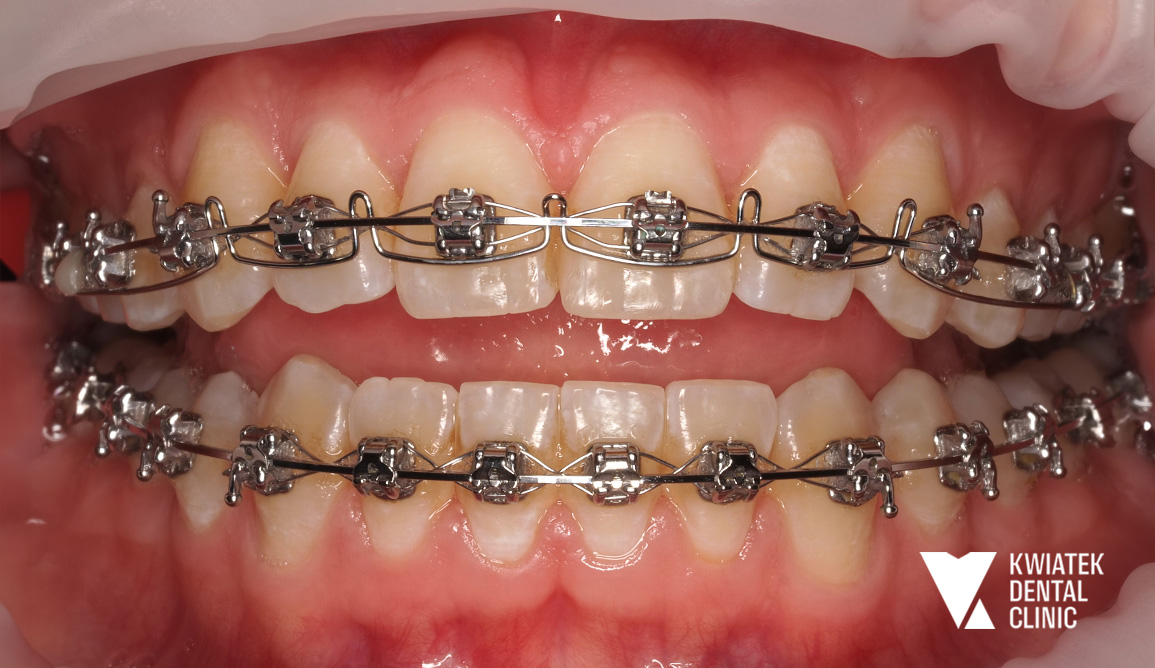

PRZED

PO

Uzyskano prawidłowe ustawienie zębów w łukach, korektę zgryzu krzyżowego, właściwą relację zgryzową oraz harmonijną estetykę uśmiechu. Metamorfoza pokazuje, jak dzięki dokładnej diagnostyce, nowoczesnym technikom ortodontycznym oraz konsekwentnemu prowadzeniu leczenia można osiągnąć stabilny i naturalny efekt bez konieczności usuwania zębów przedtrzonowych.